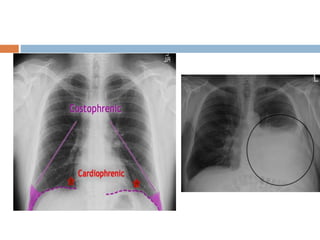

Effusion

 Look for blunting of the costophrenic angle

 Identify the major fissures, if you can see

them more obvious than usual, then this could

mean that fluid is tracking along the fissure

Pleural Effusion

 On an upright film, an effusion will cause blunting

on the lateral costophrenicsulcus and, if large

enough, on the posterior costophrenicsulcus.

 Approximately 200 ml of fluid are needed to detect

an effusion in a PA film, while approximately 75 ml

of fluid would be visible in the lateral view